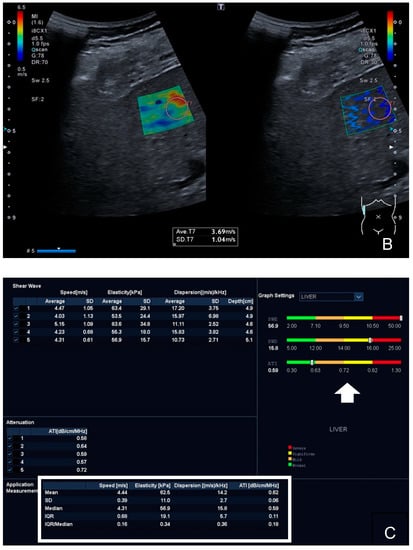

2.3. Shear-Wave Elastography

2.4. Shear-Wave Dispersion

2.5. Attenuation Imaging Technique